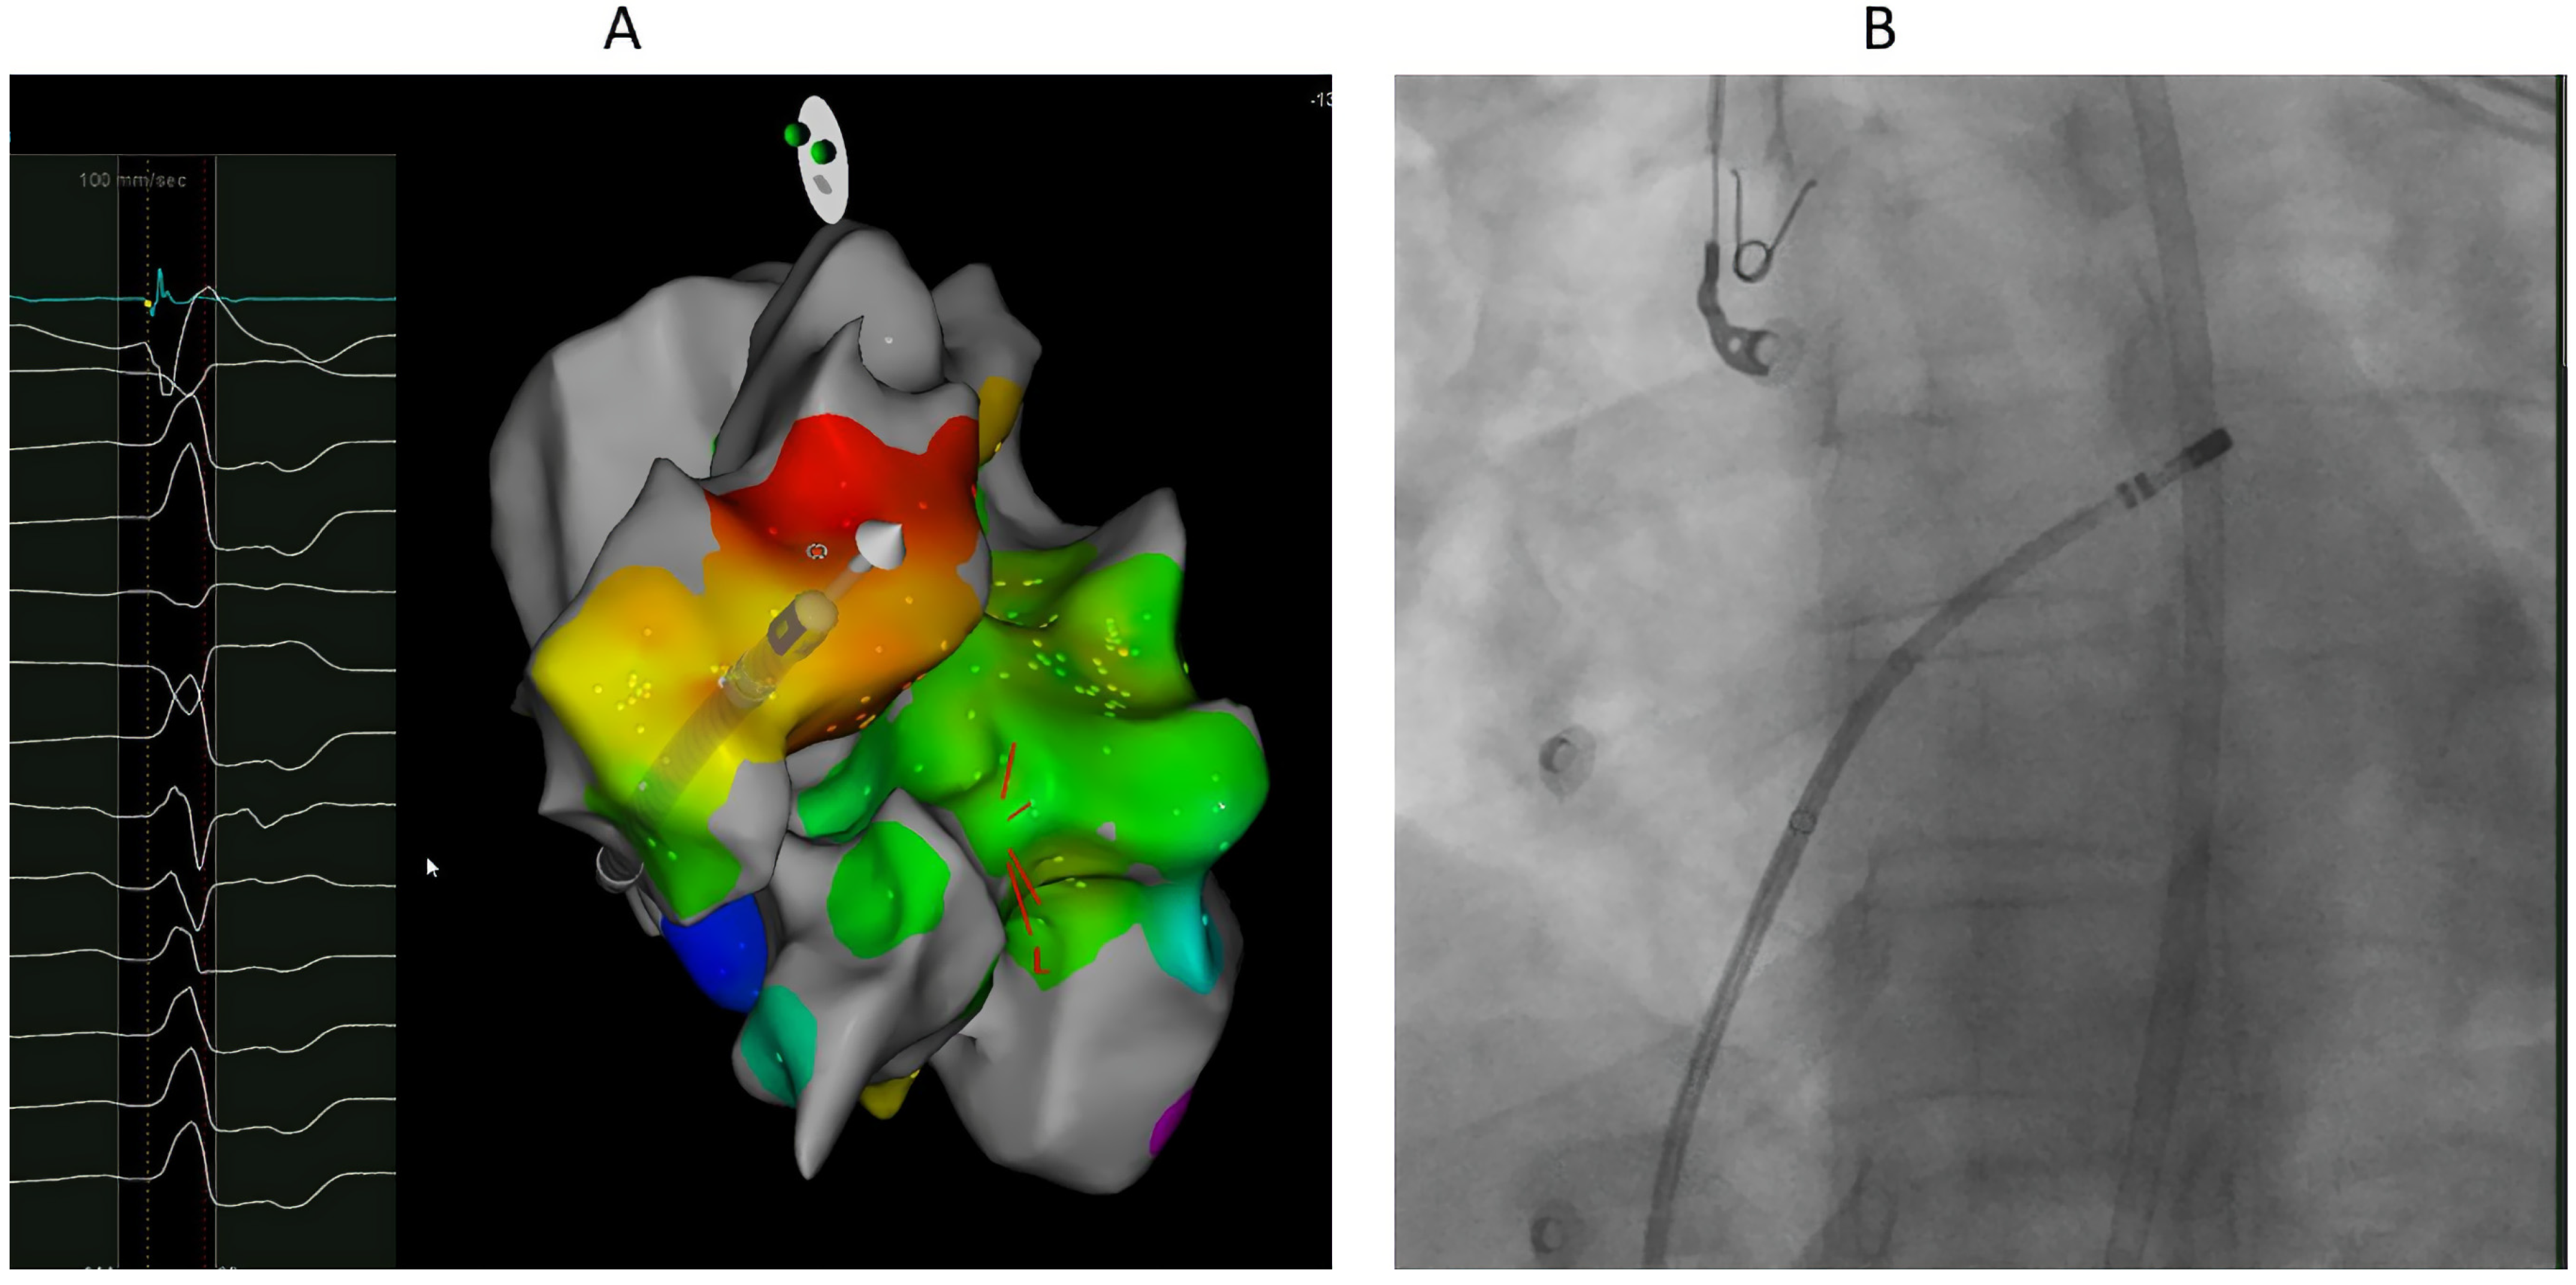

7.1. Procedure

8.2. Ablation Sites